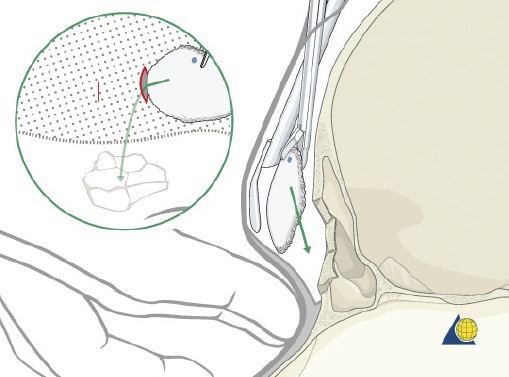

Type II fractures require more extensive surgical exposure, and generally need two- or three-point fixation. A subperiosteal dissection is used to locate, but not avulse, the medial canthal tendon. If the comminution is mild and the central fragment can be plated, the injury is treated as a type I fracture. If the central fragment is too small to be plated, transnasal wires should be used. Transnasal wires are generally easiest to place prior to any osteosynthesis of the surrounding fractures. Initially holes are drilled in the central fragment above and below the medial canthal tendon ( Fig. 63.62 ). Both ends of a 28-gauge wire (or a wire suture) are passed from lateral to medial, leaving the free ends on the medial surface of the central fragment ( Fig. 63.63 ). Once the central fragment is controlled with the wire, a drill may be used to define a transnasal path for passage of the wire ( Fig. 63.64 ). The drill must be passed posterior and superior to the lacrimal fossa, and below the frontoethmoid suture line (to avoid intracranial injury). A 14-gauge spinal needle (or angiocatheter with outer sheath removed) is then passed through the drill hole. The needle is passed in a retrograde fashion, through the ethmoid complex, from the uninjured to the injured side. A malleable retractor is placed medial to the globe on the injured side to provide protection as the spinal needle is passed. The wires are then passed transnasally through the lumen of the needle, and the needle is removed ( Fig. 63.65 ). The wire is then tightened while the central fragment is medialized with external pressure, securing the wire on a miniscrew in the frontal bone ( Fig. 63.66 ). It is critical that tension is maintained on the wire throughout fixation. Any laxity in the wire may allow the medial canthal tendon to lateralize with concomitant loss of fracture reduction. It is difficult, if not impossible, to overcorrect the reduction. Appropriate wire placement posterior and superior to the lacrimal fossa will pull the canthus medially without rotation. Transnasal wires placed anterior to the lacrimal fossa will result in lateral rotation of the central fragment and iatrogenic telecanthus ( Fig. 63.67 ).25